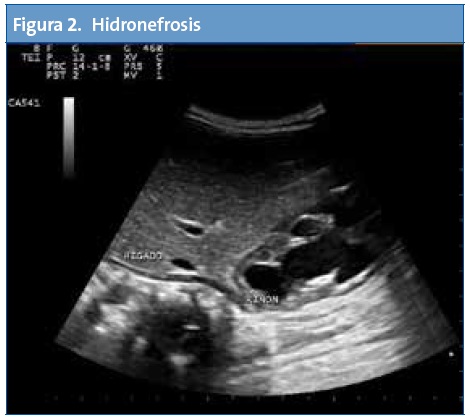

La ecografía puede ser de utilidad tanto para screening de patologías como para diagnóstico y/o seguimiento. Es una herramienta de apoyo a nuestra orientación diagnóstica basada en una clínica y una exploración física.

En Atención Primaria el mayor rendimiento se obtiene de la exploración abdominal seguida del estudio de la zona cervical, partes blandas, aparato genital, pulmón y aparato locomotor.